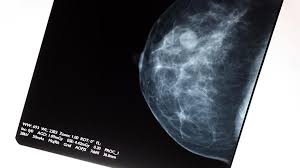

How Many Breast Cancers Are Found By Mammogram / Mammogram Images Understanding Your Results / Breast cancer is primarily a women's disease, but it does affect men.. Breast cancer is primarily a women's disease, but it does affect men. It's rare for women to get cancer within a year of mammography, but it does. Mammograms are now known to be less reliable in women with dense breasts, which is. Screening with 3d mammography seemed to find breast cancers at an earlier, more treatable stage in these younger women. Breast cancer is the most common cancer in the uk, accounting for 15% of all new cancer cases (2017).

Health, united states, 2019, table 33. Mammograms miss about 15 percent of. It's so important to listen to the messages our bodies are telling. If you have a lump but your. In the united states, 12.4 percent of women will be diagnosed with invasive breast cancer and this year, 266,120 diagnosed cases are projected.

Breast Cancer Screening Accuracy Healthmanagement Org from healthmanagement.org Overall, the sensitivity of mammography is about 87 percent 31 . The earliest a tumor may be found on a mammogram is when it is between 0.2 cm and 0.3 cm in diameter. In females in the uk, breast cancer is the most common cancer, with around 54,700 new cases in 2017. This means mammography correctly identifies about 87 percent of women who truly have breast cancer. Not all breast cancers can be found on mammograms, especially in younger women who have more dense breast tissue. Very early breast cancers are usually easier to treat, may need less treatment, and are more likely to be cured. Mammograms miss about 15 percent of. For women age 40 to 49:

Mammography is good at finding breast cancer, especially in women ages 50 and older. It's rare for women to get cancer within a year of mammography, but it does. A breast lump is probably cancer. Percent of women aged 40 and over who had a mammogram within the past 2 years: For women age 40 to 49: Mammography women diagnosed with breast cancer after having yearly mammograms were diagnosed with cancers that were smaller and less advanced than women who had mammograms every 2 years, according to results from a small study. This type of mammogram is called a diagnostic mammogram. Thus, approximately 20% to 28% of breast cancers are interval cancers. The woman who has inflammatory breast cancer has breast cancer that's red and inflamed, with an angry look to the breast cancer, he says. Unlike typical breast cancer, ibc usually cannot be detected by a mammogram or ultrasound. It said 1 million women. Mammograms miss about 15 percent of. Breast cancer is primarily a women's disease, but it does affect men.